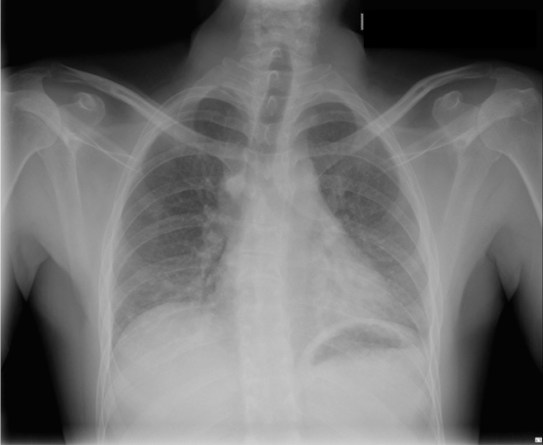

CASO: Operada de esofaguectomia y reconstrucción con coloplastia hace 3 meses. Sintomas de neumonía.

Hallazgos:

- De inicio llama la atención una densidad practicamente total del todo el hemitórax izquierdo, lo cual podría hacernos pensar que estamos ante una posible neumonía.

- Sin embargo el tórax está no está bien centrado, observar como la clavícula izquierda se encuentra casi en la mitad del pulmón, por tanto lo que vemos blanco es el mediastino ya que el tórax está rotado.

CENTRAJE:

El correcto centraje se determina comprobando que las extremidades internas de ambas clavículas equidistan de las apófisis espinosas vertebrales.

Mismo paciente, al cual esta vez se le ha tomado una radiografía en PA y en sedestación. Observar como las clavículas están equidistantes a las apófisis espinosas y como ha desaparecido el velamiento del pulmón izquierdo.

Por otra parte, paciente presenta una cardiomegalia y un discreto ensanchamiento del mediastino es probable relación con cambios postquirúrgicos.